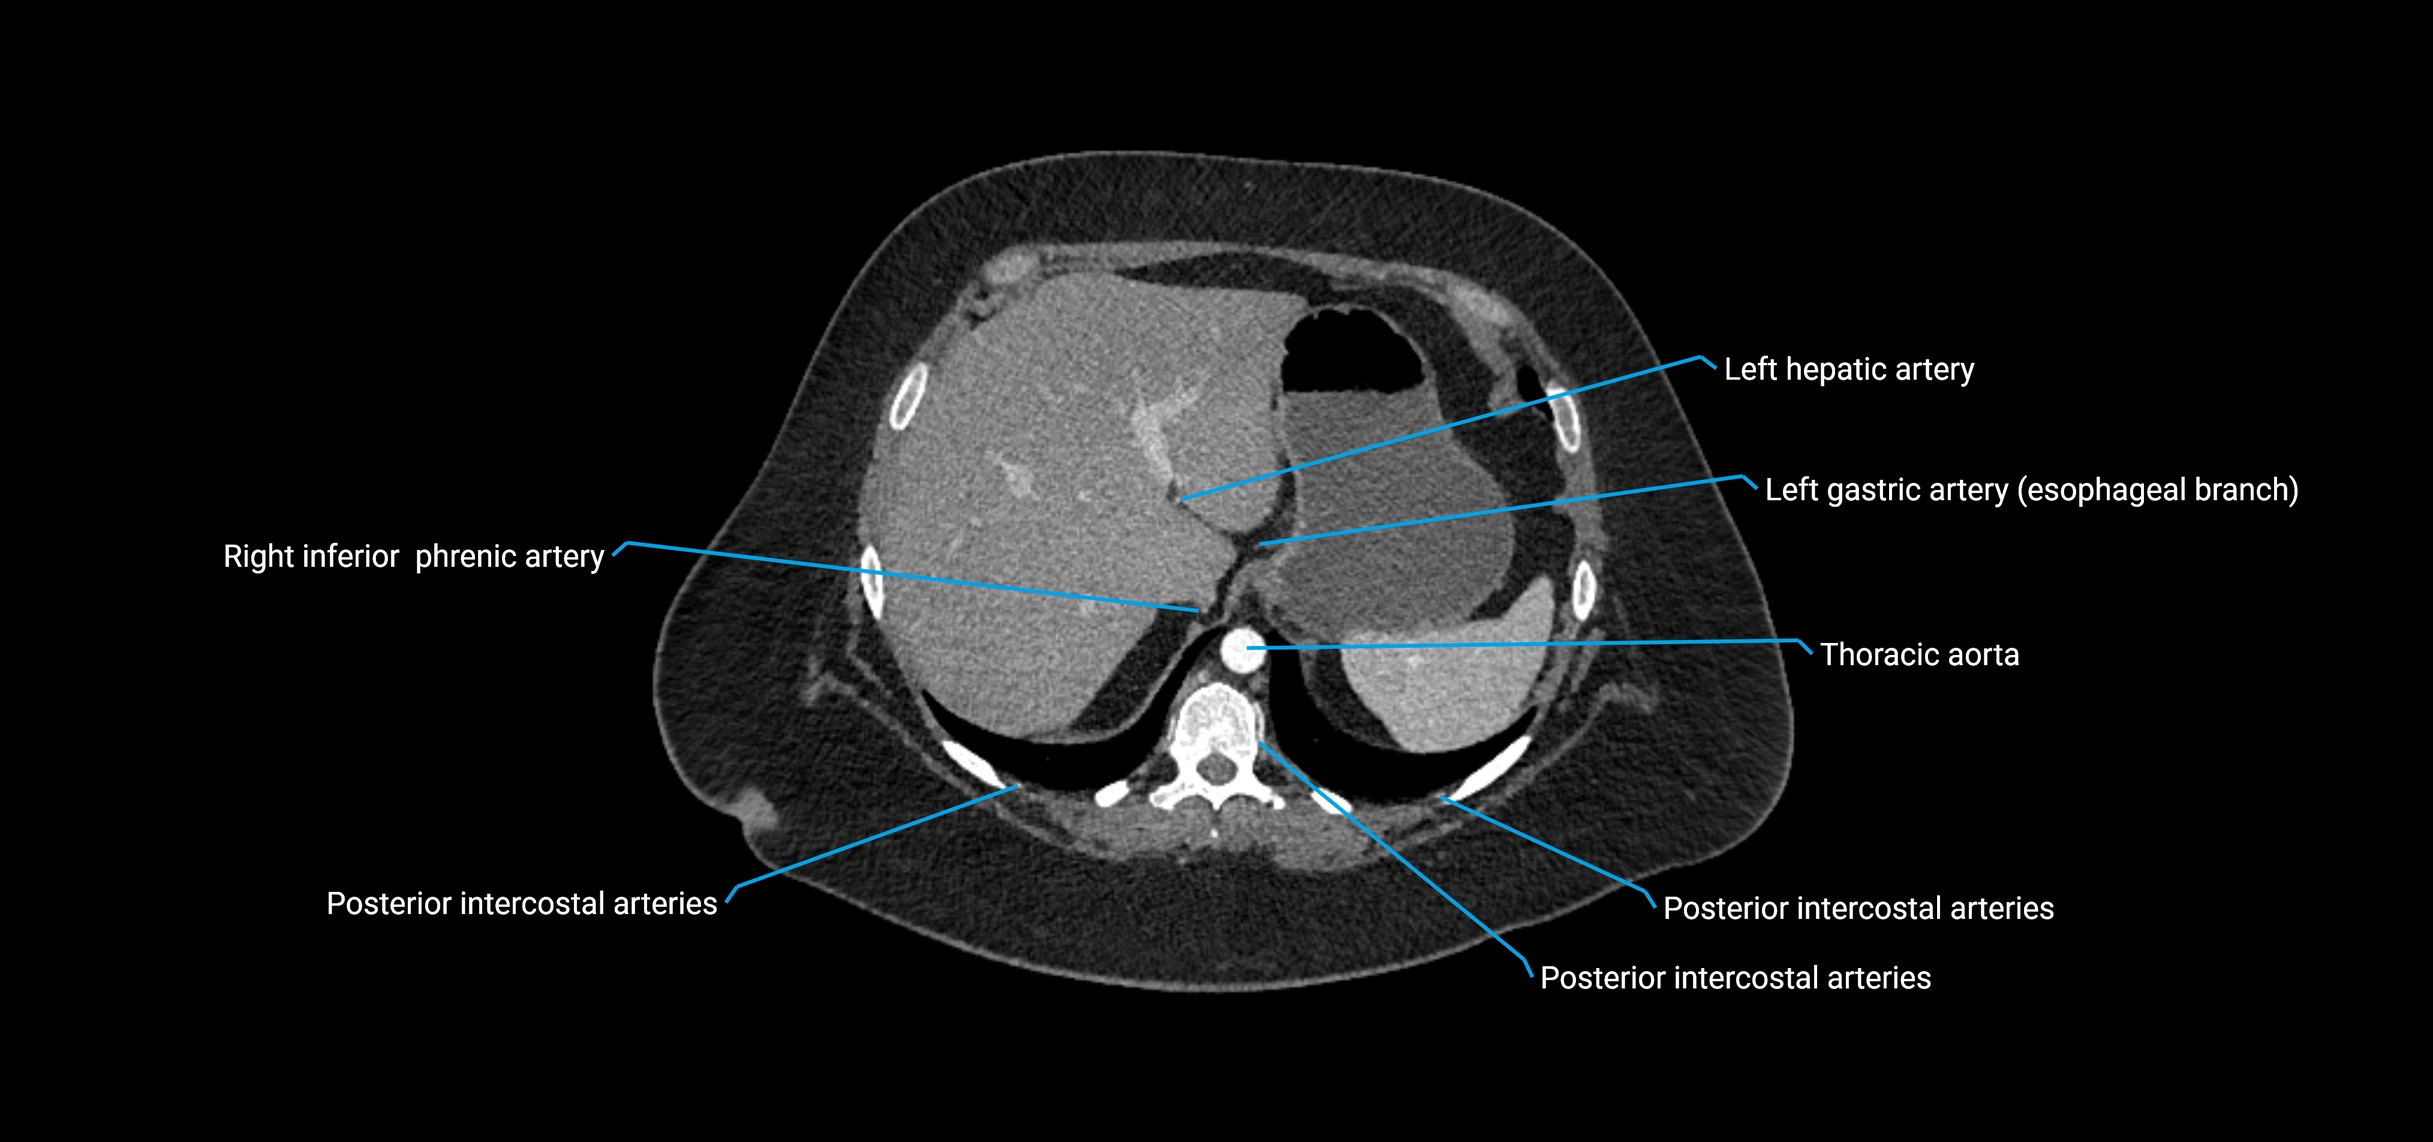

Contrast-enhanced CT (CTA):

• Gold standard for abdominal aortic imaging

• Provides excellent detail of lumen, wall, aneurysm, thrombus, and branch vessels

• Multiplanar and 3D reconstructions help in aneurysm measurement, stent graft planning, and dissection evaluation

The abdominal aorta is the continuation of the thoracic aorta, beginning at the level of the aortic hiatus of the diaphragm (T12 vertebra) and terminating at the level of the L4 vertebra where it bifurcates into the right and left common iliac arteries. It lies slightly to the left of the midline and courses anterior to the vertebral bodies, surrounded by the retroperitoneal structures of the abdomen.

The abdominal aorta gives off numerous visceral and parietal branches, supplying the abdominal organs, pelvic structures, and lower limbs. It is the main conduit of oxygenated blood from the heart to the abdomen and lower body. The aorta is clinically significant as the common site of aneurysm, dissection, atherosclerosis, and traumatic injury.